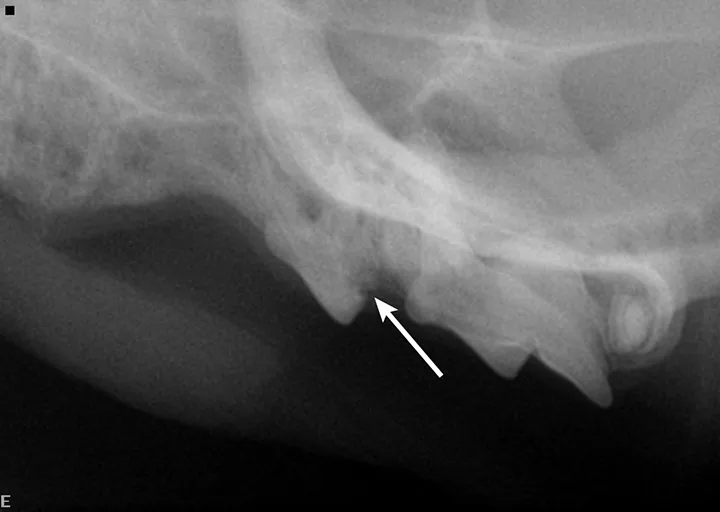

FIGURE 3

Intraoral radiograph of the left maxilla revealing type 2 tooth resorption on the third premolar (arrow). Extraction is indicated.

A complete oral examination and full-mouth dental radiographs were performed with the patient anesthetized. The detailed oral examination confirmed unhealed extraction sites with sharp crown fragments protruding from the alveoli into the oral cavity. In addition, an advanced TR lesion was noted affecting the left maxillary third premolar tooth (Figure 3). Dental radiographs confirmed advanced type 2 resorption affecting all involved teeth, as well as oral extension of the remaining tooth structure (Figure 4).